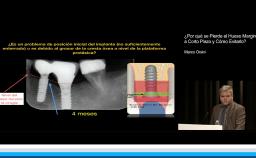

Esta presentación introduce de una forma didáctica y clínica los principales aspectos que han sido actualizados en la segunda version de la Clasificación SAC y en consecuencia en la herramienta de Evaluación SAC V2 basada en dicha clasificación. Adicionalmente, durante la sesión se demostrará mediante la presentación de interesantes casos clínicos como implementar dicha herramienta para la evaluación de riesgos en distintos escenarios.

• Implementar el concepto de la evaluación de riesgo pre-tratamiento en la práctica clínica contemporánea con implantes dentales

• Reconocer las principales actualizaciones de la herramienta de evaluación SAC V2 y su aplicación clínica en la implantología moderna

• Conocer a través de la presentación de distintos escenarios clínicos las herramientas que proporciona el ITI para evaluar el nivel de riesgo de complicaciones en pacientes con alta demanda estética